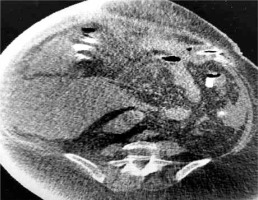

In our case, a gastrostomy was created to the bypassed stomach (Fig. 1) in order to improve nutritional status, reverse SIBO and enhance the immune system, an approach which is suggested by some authors [16]. In high risk patients for development of aggressive steatohepatitis after bariatric surgery, more attention is needed to the rate of weight reduction and therefore to the choice of bariatric procedure. LL-RYGB, BPD and duodenal switch appear to correlate with a higher rate of hepatic complications due to the rapid weight loss they provoke [17]. The rate of BMI reduction cannot be predicted but studies show that a reduction > 1.6 kg/day leads to deterioration of steatohepatitis and fibrosis, especially in patients with high BMI [18].